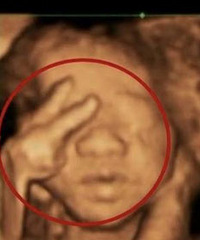

男婴被高空坠物砸中头部

最新消息,柯桥被高空坠物砸中的那个14月龄宝宝,已脑死亡,痛心,孩子才14个月!3月5日,浙江绍兴市柯桥区待驾桥花园一14月龄男宝宝被高空坠落砖块砸中头部。3月6日晚,宝宝仍在浙江大学医学院附属儿童医院救治。记者从宝宝家人处了解到,虽经紧急手术,但孩子脑部已死亡,目前靠